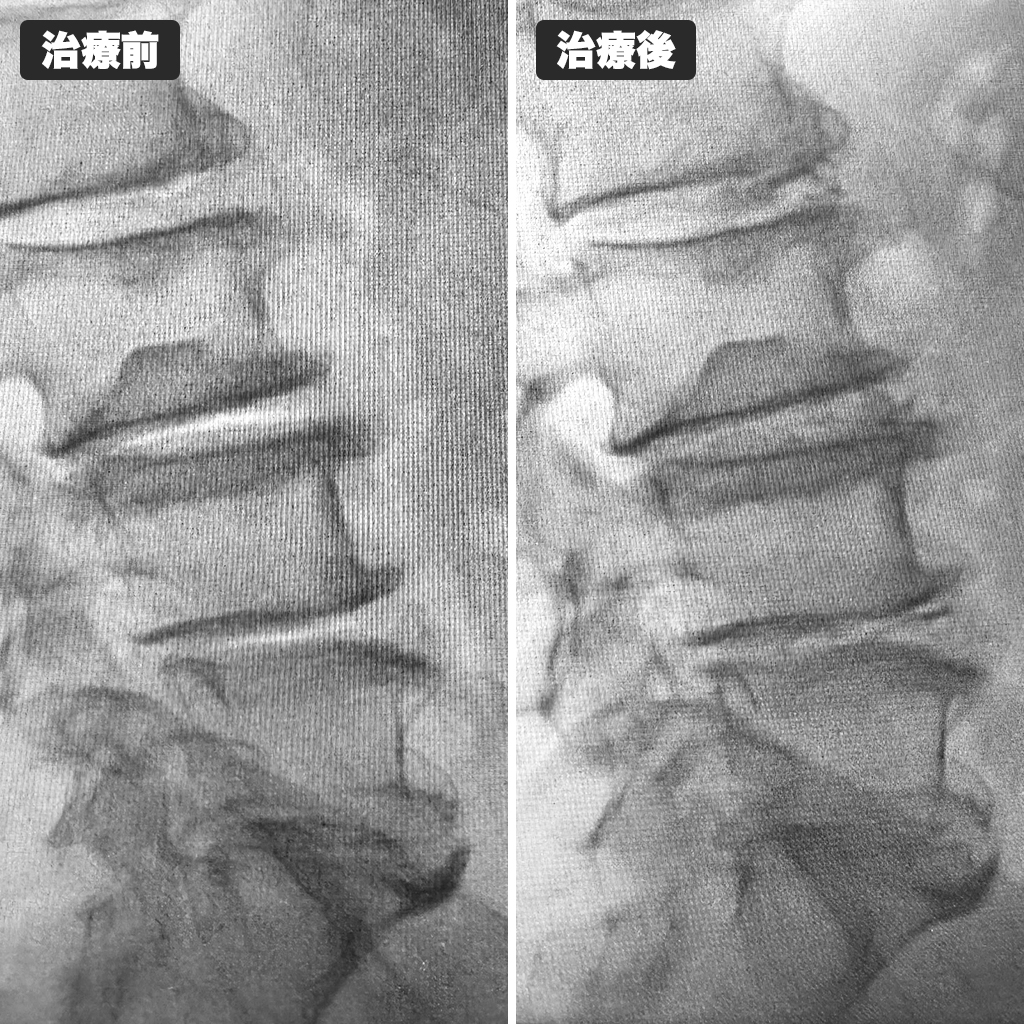

椎間板検査(Annulogram検査)を行っているところになります。繊維輪の損傷が確認され、予定通りディスクシール治療を行っています。

治療前後のレントゲン写真です。左側が治療前、右側が治療後になります。